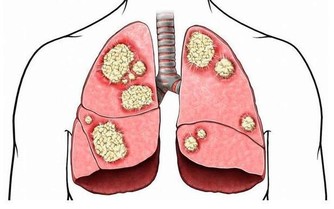

腎病進展到慢性腎功能衰竭階段(俗稱尿毒症)時,患者口中、呼出的氣體中常帶有尿味。

這是因為,此時尿素無法被正常代謝,瀦留體內,導致呼吸散發出尿味。